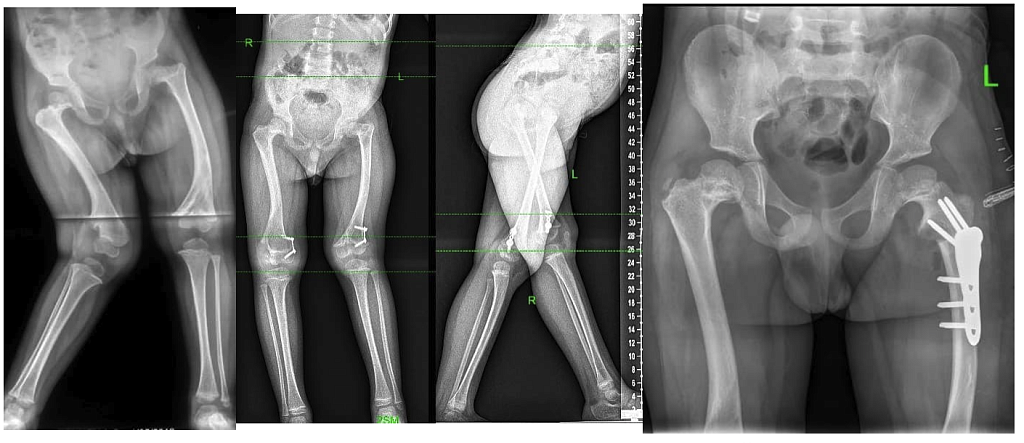

Последствие острого гематогенного остеомиелита (ПОГО), до операции

Через 2 года После второй операции